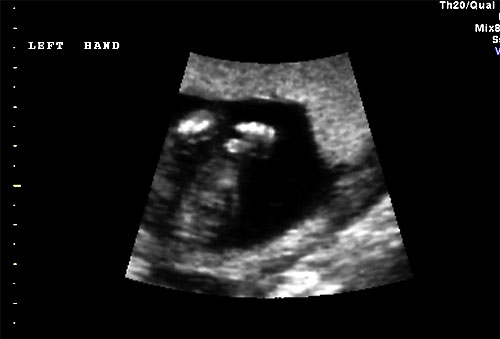

Normal 16 week left hand |